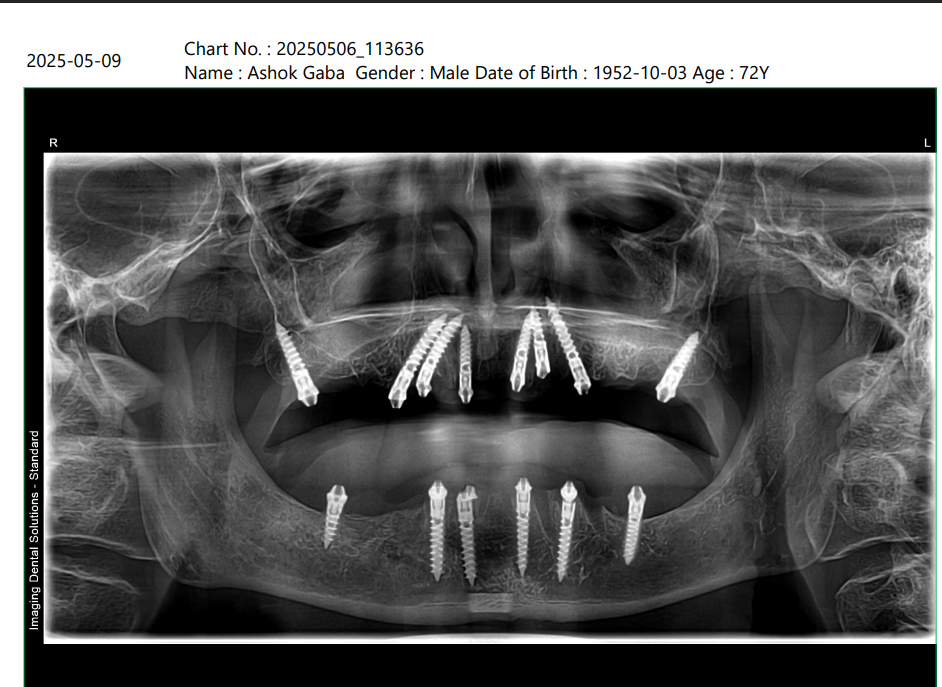

X-Ray Analysis

OPG — After

Radiographic Findings

Multiple implants placed in both upper and lower jaw Implants are strategically angled and distributed Strong anchorage in available bone Proper full arch support for fixed teeth Balanced load distribution 👉 Clinical Meaning (simple explanation): We have created a strong foundation using implants, which act like artificial roots. These implants support fixed teeth, allowing the patient to chew normally again.